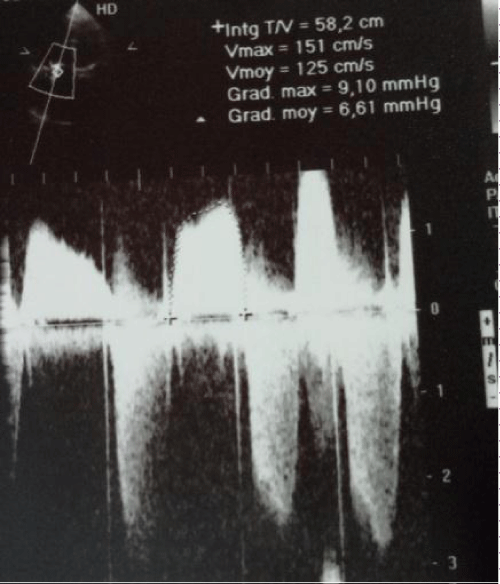

A 62 year old woman presented with right sided heart failure symptoms encluding dyspnea, lower exteremity edema fatigue and ascites. She had a history of mitral stenosis since the age of 10. She had originally under gone mitral and aortic valve replacement at the age of 40, along with a tricuspid valve annuloplasty with a carpentier Edwards tricuspid ring for severe tricuspid regurgitation (TR). Ten year later she under went a tricuspid valve replacement with a bioprothesis due to persistant of severe tricuspid regurgitation. She remained a symptomatic until the age of 61, her fatigue increased and lower extreme tyedema worsened when she was admitted to hospital. The physical examination revealed signs of right heart failure of right heart failure. The patient was on atrial fibrillation. The echo cardiogram revealed severe thickened leaf lets of the bioprothetic tricuspid valve, with a severe tricuspid stenosis and mild regurgitation. The mean diastolic gradient across the tricuspid valve was 12 mmHg (Figure 2).